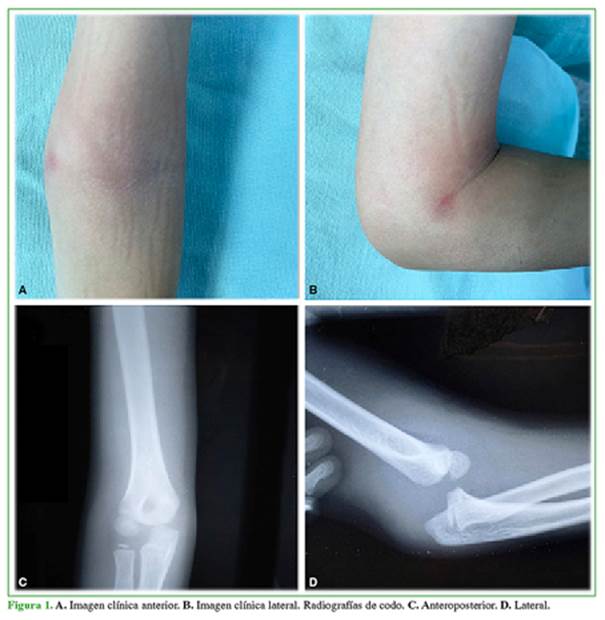

Niño de 6 años, sin antecedentes clínicos, que se había caído de un árbol con el codo en hiperextensión. A las ocho horas de la caída, consultó en el Departamento de Urgencia con dolor y deformidad en el codo derecho. En la evaluación inicial, se observó una lesión cerrada, asociada a edema lateral y posterior, deformidad con rangos de movilidad abolidos. El pulso radial era palpable, la mano tenía un llenado capilar <2 segundos y no había déficit sensitivo. En el examen físico y las radiografías del codo lesionado (Figura 1), se observó una luxación posterior de codo derecho aislada.